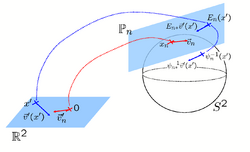

Spherical Demons: Fast Surface RegistrationWe present the fast Spherical Demons algorithm for registering two spherical images. By exploiting spherical vector spline interpolation theory, we show that a large class of regularizers for the modified demons objective function can be efficiently approximated on the sphere using convolution. Based on the one parameter subgroups of diffeomorphisms, More... New: B.T.T. Yeo, M.R. Sabuncu, T. Vercauteren, N. Ayache, B. Fischl and P. Golland. Spherical Demons: Fast Diffeomorphic Landmark-Free Surface Registration. IEEE Transactions on Medical Imaging, 29(3):650-668, 2010.